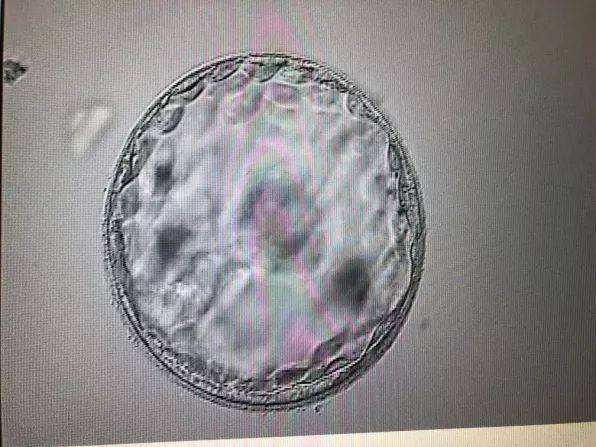

当受精卵成功着床后,孕妇的体内会发生一系列生理变化,这些变化是怀孕一星期左右有什么症状吗的重要信号。